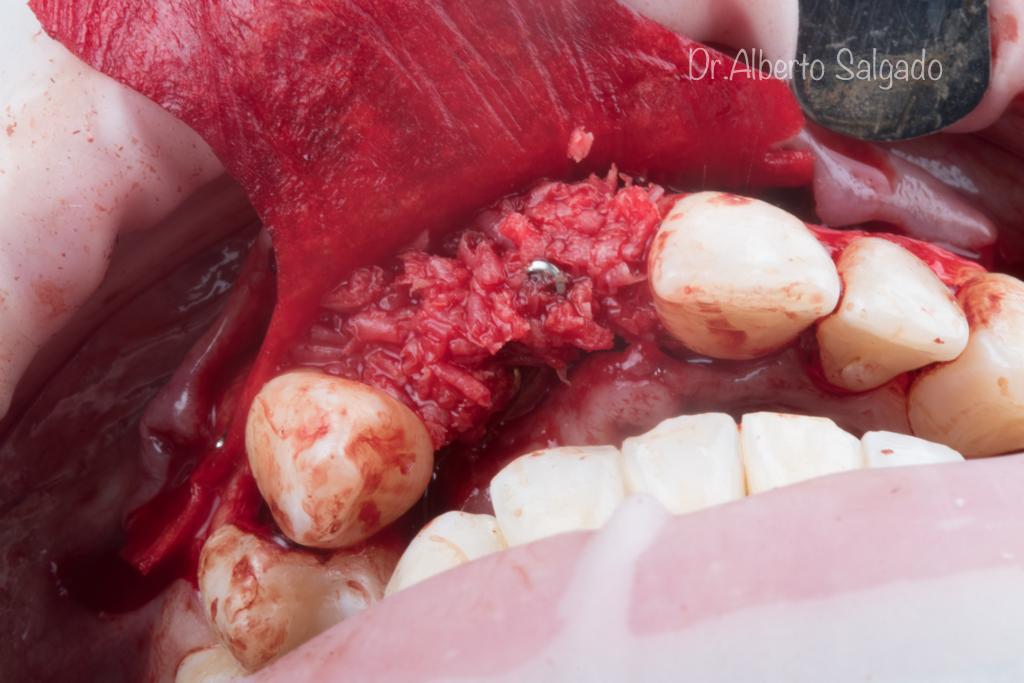

Dr. Alberto

Salgado